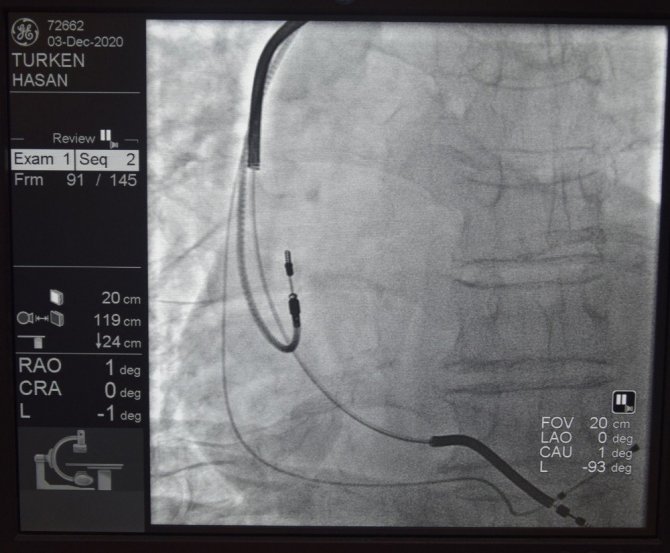

Kardiyak Resenkronizasyon tedavisi, ağır kalp hastalarının şikayetlerini azaltarak yaşam sürelerinin uzamasını katkı sağlıyor. Az sayıda merkezde yapılabilen tedavi merkezini başarı ile uygulayan Düzce Üniversitesi Hastanesi Kardiyoloji Anabilim Dalı ise tedavi ile ağır kalp yetmezliği hastalarına umut oluyor. Merkezin tedavi yöntemini duyan 78 yaşındaki Hasan Türken de hastaneye gelerek tedavi olmak için Kardiyoloji Polikliniğine başvurdu. Türken'in yapılan tetkik ve değerlendirmeler sonrası Kardiyak Resenkronizasyon tedavisi uygulanmasına karar verildi. Düzce Üniversitesi Tıp Fakültesi Kardiyoloji Anabilim Dalı Başkanı Doç. Dr. Osman Kayapınar ve ekibi tarafından yapılan operasyon sonrası sağlığına kavuşan hasta Türken, taburcu edildi.

Az sayıda merkezde uygulanan tedavi yöntemi hakkında bilgiler veren Doç. Dr. Osman Kayapınar, kalbin ileti sistemlerinde meydana gelen bazı bozuklukların, kalpte senkron kasılmayı bozarak, kalp fonksiyonlarının olumsuz etkilenmesine neden olduğuna dikkat çekti. Kardiyak Resenkronizasyon tedavisi ile üç odacıklı özel pacemaker sistemleri vasıtasıyla ventrikül içi ileti gecikmesine bağlı gelişen dissenkroniyi ortadan kaldırılabildiğini ve kalp fonksiyonlarının düzeltilerek senkron çalışmasının sağlandığını ifade eden Doç. Dr. Kayapınar, Düzce Üniversitesi Hastanesi'nde bütün kalp pili uygulamaları gibi Kardiyak Resenkronizasyon tedavisinin de (KRT) başarıyla uygulandığını vurguladı.